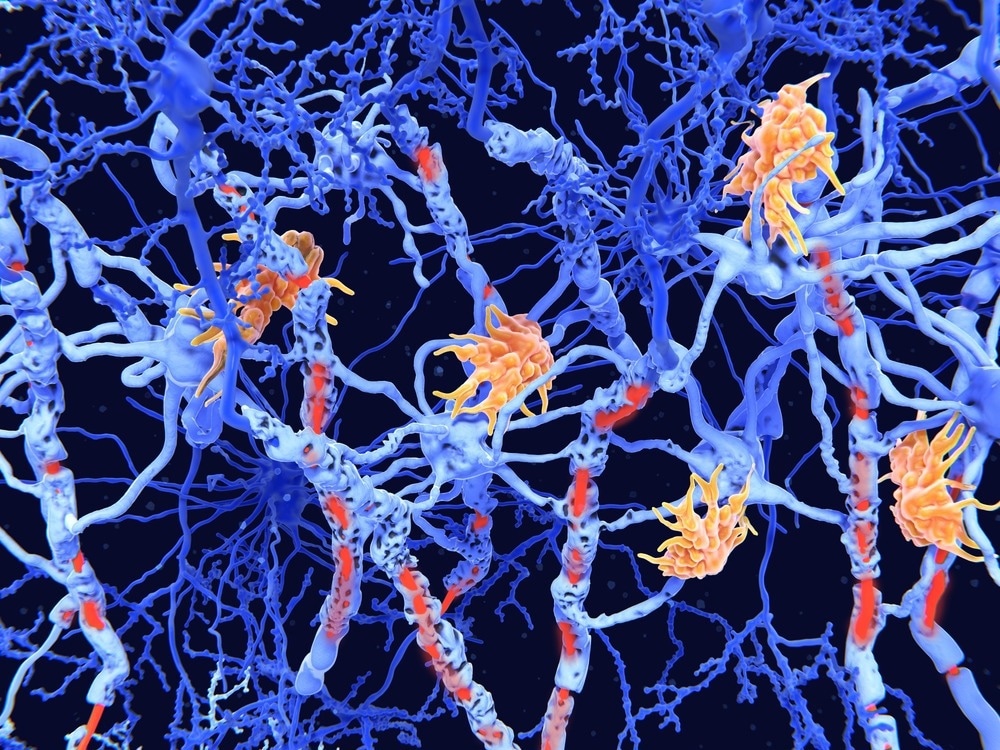

מחקר פורץ דרך מפרט כיצד נישות רקמות שונות ותקשורת תאים תורמים לנגעים פעילים כרוניים בטרשת נפוצה. מחקר: מיפוי סוג תאים